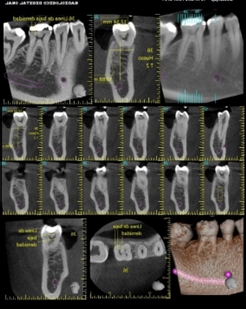

Supernumerario - Reabsorción Radicular

En el caso de un diente supernumerario, es esencial conocer su ubicación precisa y su relación con otras estructuras dentales…

La Hiperdoncia

Nuestra dentadura tiene 28 piezas dentales cuando somos niños y 32 piezas en la edad adulta, incluidas las muelas del juicio. Sin embargo, algunos humanos tienen más piezas de las habituales…